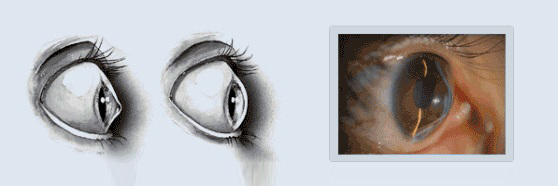

드림렌즈란 특수디자인된 렌즈로 원하는 도수만큼 각막 중심부에 자극을 주어,각막 형태를 변화시켜

근시,난시의 진행을 억제시켜주는 렌즈이며 특히 성장기 학생들에게 효과가 탁월합니다.